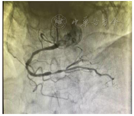

冠脉动脉造影:呈右优势,LAD血管内串联2个支架通畅,支架内无再狭窄,LCX近段最重处狭窄<30%,支架通畅,支架内无再狭窄,RCA中远段弥漫性狭窄70%~90%(图2)。

患者第3次造影,LAD与LCX支架通畅,RCA中远段狭窄70%~90%,狭窄程度较前两次造影加重,遂于RCA置入支架1枚。